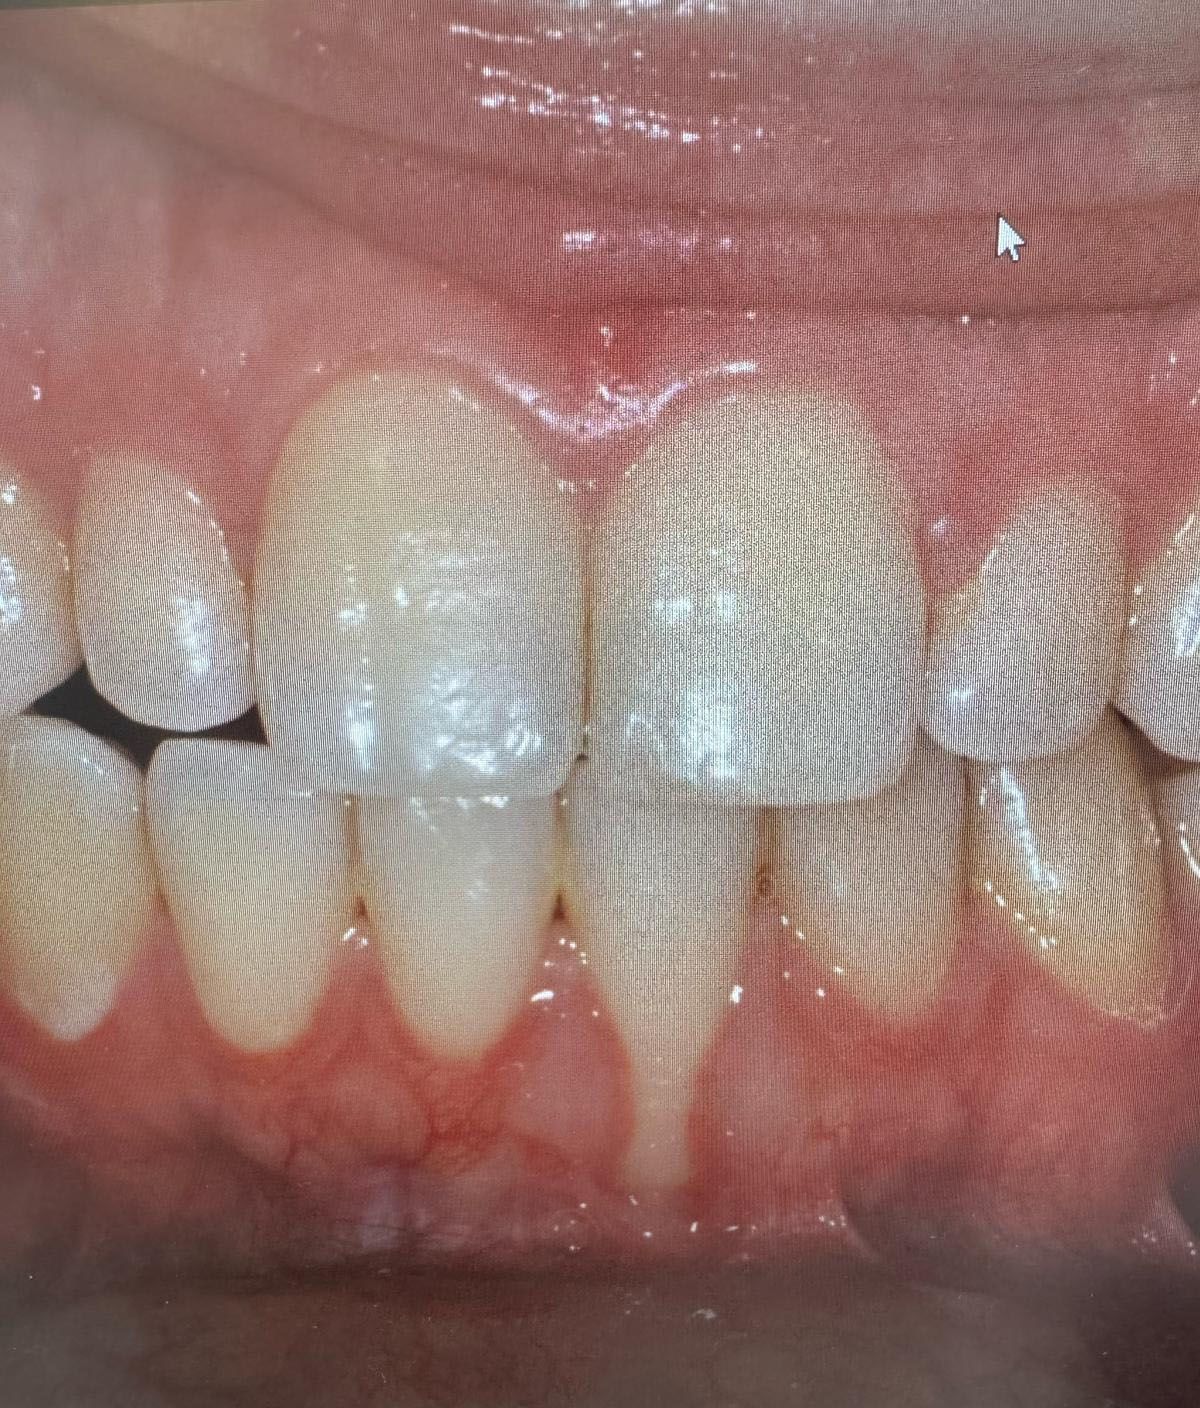

E' una procedura chirurgica che ha lo scopo di ricostruire (immagina 2) il volume osseo mancante e/o insufficiente (immagine 1), in alcune zone dell'osso alveolare dell'arcata dentale. Permette, dopo la rigenerativa dell'osso, di posizionare un impianto dentale (immagine 3) o di eliminare una tasca ossea adiacente ad un elemento dentale.